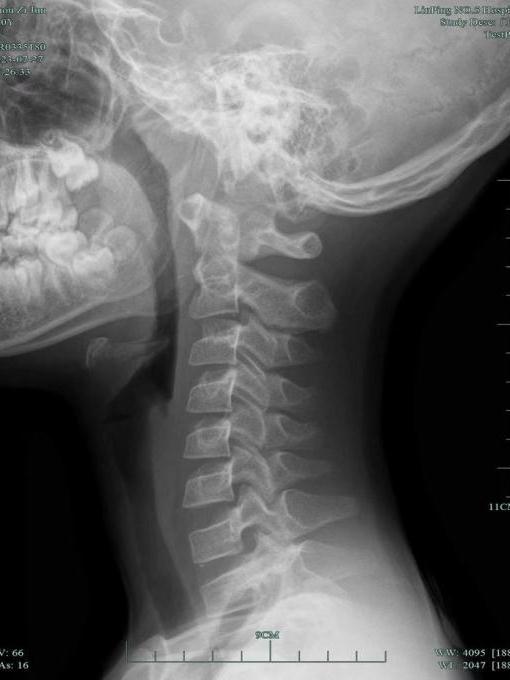

王主任查看小杰的頸部DR片驚訝地吐出四個字:一塌糊涂!

小杰頸椎病變嚴重,小關節錯位,頸椎反弓。明明才10歲,頸椎已經跟30歲的人一樣,老化程度甚至超過不少接診的成年人。